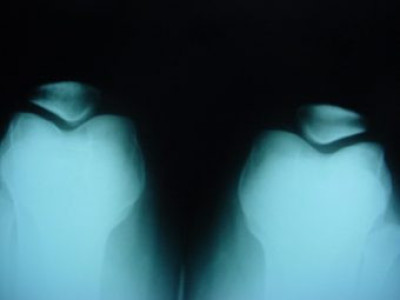

Luxación Habitual de Rótula

Envíado por Dr. Eduardo E. Martínez Melara